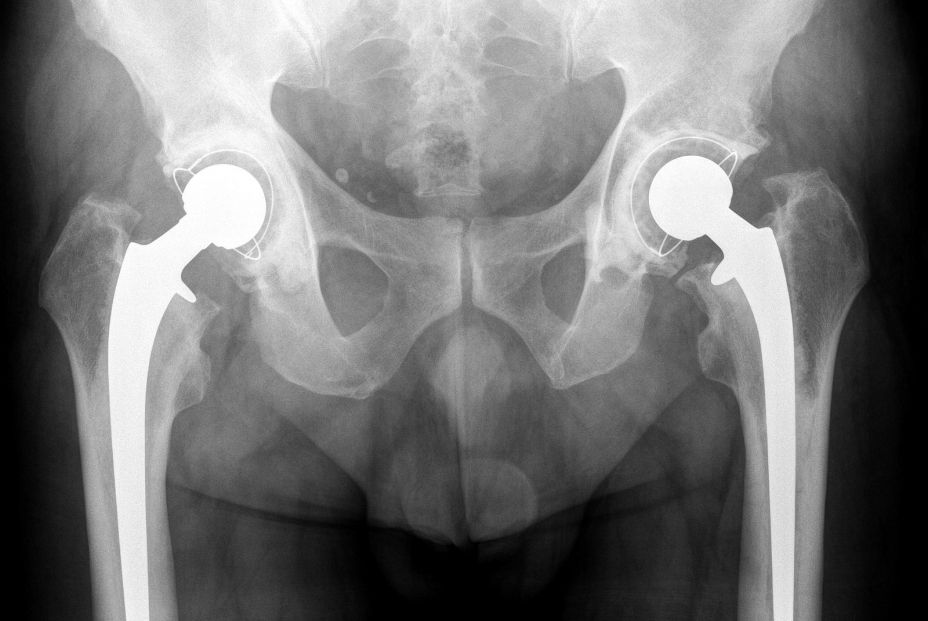

Dispositivos articulares

Los dispositivos articulares son prótesis (artroplastias). Las de cadera y rodilla son las más comunes; también las hay de hombro, codo o tobillo. Se usan en fases avanzadas de artrosis y otras enfermedades degenerativas del aparato locomotor, en cirugía oncológica y en fracturas de cadera del anciano.

Las infecciones articulares son poco frecuentes, aunque van al alza por el mayor número de implantes que se colocan cada año. El 1%-2% de las prótesis primarias se infecta, siendo el riesgo es mayor en revisiones, cirugías urgentes o pacientes con comorbilidades.

"Los factores de riesgo incluyen comorbilidades significativas, obesidad, antecedentes de infección e inmunosupresión. Y las consecuencias son hospitalizaciones largas, tratamientos antibióticos extensos, pérdida funcional y una carga económica importante para la sanidad", expone Jaime Lora-Tamayo, del Servicio de Medicina Interna, del Hospital Universitario 12 de Octubre de Madrid.

El tratamiento combina siempre cirugía y antibióticos. La sola administración de antimicrobianos resulta insuficiente debido a la formación de biopelículas y a la infección intracelular que actúa como reservorio. Por ello, se requiere un enfoque multidisciplinar con traumatólogos, microbiólogos y clínicos expertos en enfermedades infecciosas.

Con frecuencia es necesario retirar la prótesis; sin embargo, en algunos pacientes se puede intentar un tratamiento conservador con retención del implante (estrategia DAIR, del inglés debridement, antibiotics, and implant retention). La retirada de la prótesis se sigue de un recambio por un nuevo implante, que puede requerir una o dos cirugías. Si la reimplantación no es posible, el paciente queda con una artroplastia de resección que limita su funcionalidad.